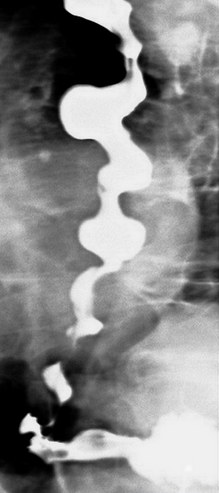

Gastrografin swallow - Colonojejunal anastomosis following esophagogastrectomy for extensive esophageal and gastric burns (Courtesy Dr. V. Penopoulos)